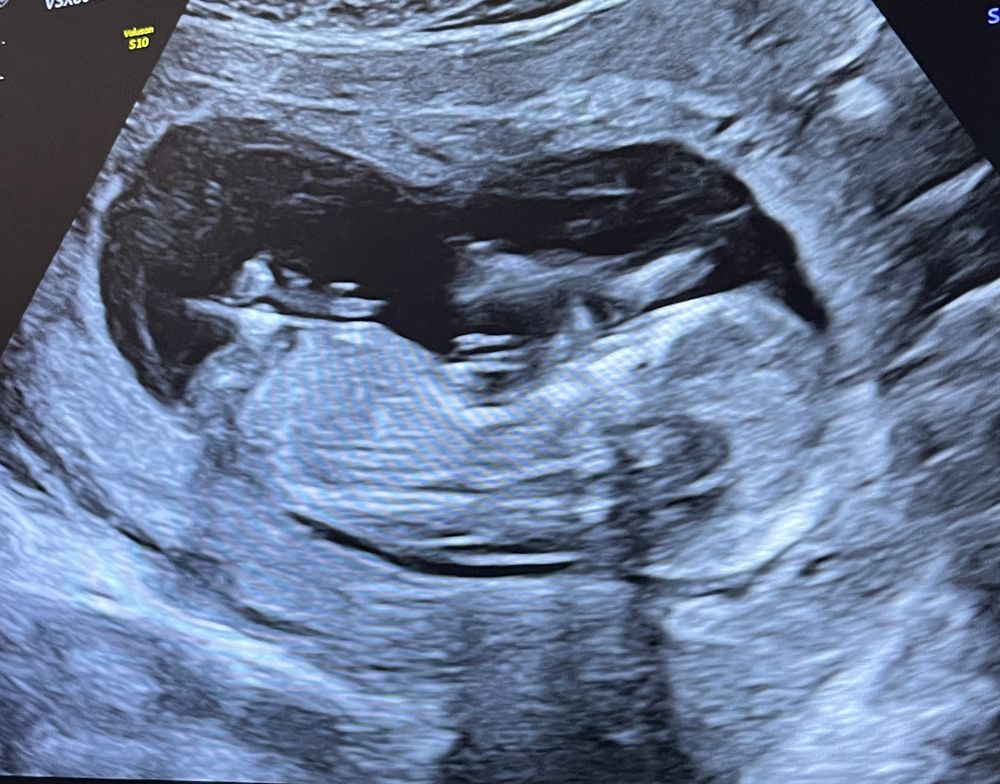

Тут не видно, половой бугорок на этом снимке узи не просматривается

Айсо, ну здравствуйте! Каким образом его может быть видно сквозь ноги? У вас же ребёнок не прозрачный 😄Это просто тень на снимке, но точно не половой бугорок)

Айсо, посмотрела, но тоже нет того ракурса на снимка, ребёнок прячет всё. Потерпите немного, скоро всё узнаете)

Но если нет сил терпеть до 2 скрининга, можно сходить платно на узи по определению пола)